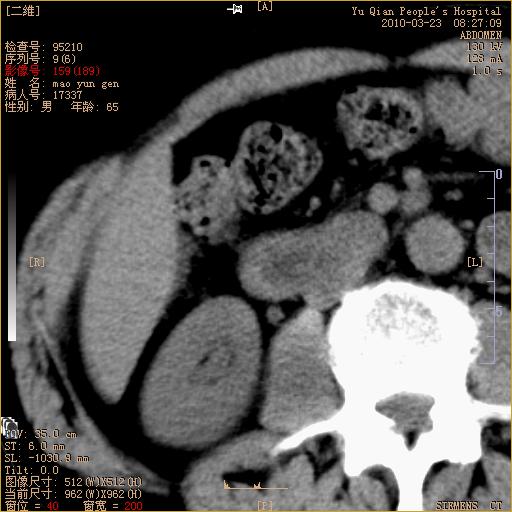

标题: CT25266:消瘦月余,前来肝部检查,请看看肠腔 [打印本页]

标题: CT25266:消瘦月余,前来肝部检查,请看看肠腔

肝区结肠占位,腺癌可考虑,建议肠镜活检。

升结肠肠壁增厚,不均强化,考虑升结肠腺癌可能性,建议肠镜检查。

1)考虑升结肠癌。2)右肾小囊肿。